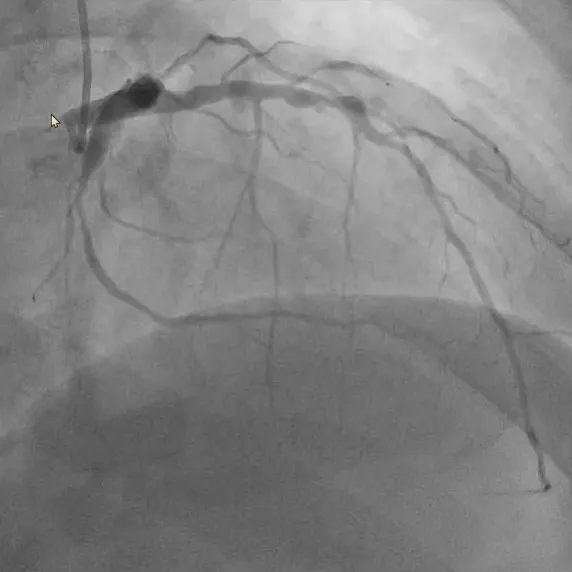

首例患者为一名患有冠心病的52岁男性,经术前冠脉造影检查显示左冠前降支和回旋支均有80%以上狭窄病变,需进行支架植入治疗,在与患者充分沟通并签署知情同意书后,手术顺利实施。

基线造影—左冠前降支

本次手术涵盖了机器人辅助下的冠脉造影及支架植入全流程。窦克非主任医师通过机器人系统,成功完成了导管全程递送及钩冠、导丝通过病变、球囊预扩张、支架精准释放及球囊后扩张等关键步骤。手术中最引人注目的是机器人系统的全流程辅助和多通道多器械协同操控能力。医生可根据病变特点和手术需要,选择导丝和导管独立操控或同步联动,双导丝和双球囊/支架导管同时操控,大幅提升了操作效率。

术后即刻造影显示,支架扩张、贴壁良好无残余狭窄,TIMI血流3级,手术效果显著。

术后造影—左冠前降支